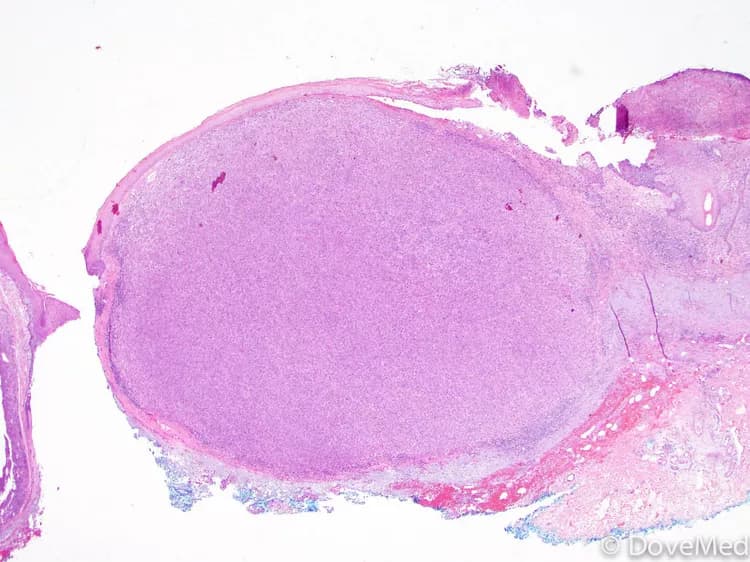

Nodular Melanoma of Skin: Nodular melanoma is a more aggressive subtype of melanoma that grows more rapidly and presents as a raised nodule. It is often blue-black or reddish in color and may bleed or ulcerate. Early diagnosis and prompt treatment are crucial due to its rapid growth and higher potential for metastasis.